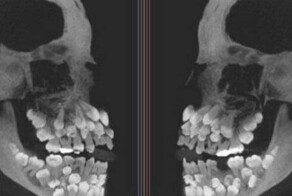

10. «У моего зуба длинные корни»